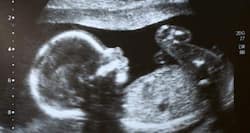

The practice of examining pregnant women using ultrasound is called obstetric sonography, and is widely used. In physics, 'ultrasound' refers to sound waves with a frequency too high for humans to hear. The sound reflects and echoes off parts of the tissue; this echo is recorded and displayed as an image to the operator.

It provides images in real-time (rather than after an acquisition or processing delay), it is portable and can be brought to a sick patient's bedside, it is substantially lower in cost, and it does not use harmful ionizing radiation. Drawbacks of ultrasound sonography include various limits on its field of view including difficulty imaging structures behind bone, and its relative dependence on a skilled operator.

in your prenatal stage, your doctor will talk about various diagnostic check-ups to ensure the status of your health and that of your unborn baby. One important reason is to check for a chromosomal abnormality like Down syndrome.